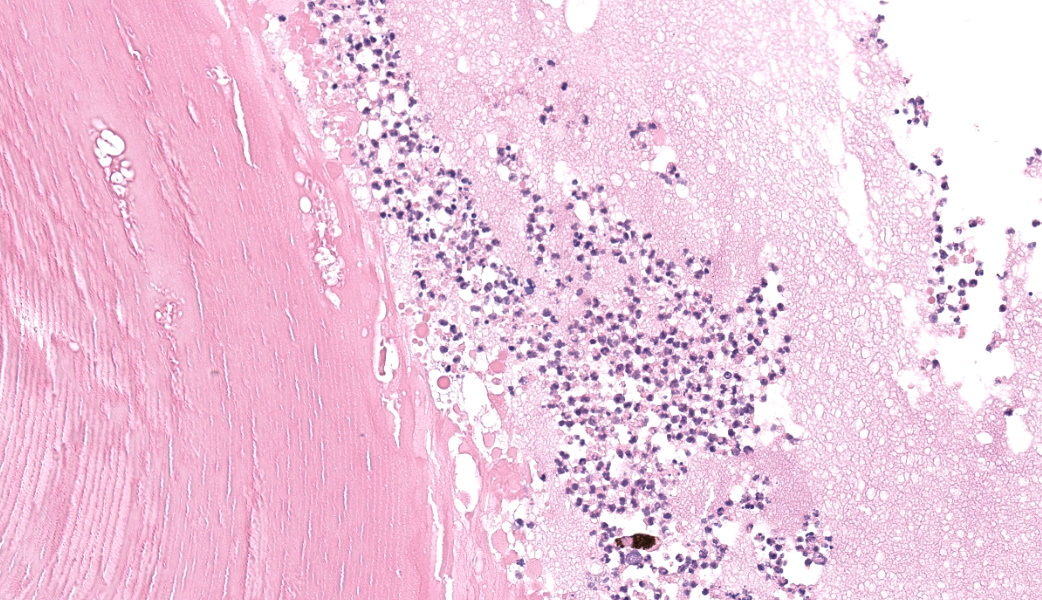

Filling all ocular chambers and coating the surfaces of intraocular structures are vast accumulations of exudate consisting of myriad degenerate and intact neutrophils, many macrophages, abundant amounts of fibrinous to proteinic material, abundant necrotic cellular debris, occasional pools of extravasated erythrocytes, and multifocal colonies of mixed bacteria (rods and coccobacilli). Centrally incorporated into the inflammatory exudates is a ruptured lens which lacks a capsule in many areas and has highly undulating free capsule margins regionally. The lenticular stroma is variably vacuolated with the following features: streaks of pallor, Morgagnian globules, many infiltrating leukocytes (mostly neutrophils), and occasional pockets of similar bacteria. The retina is diffusely detached and largely inapparent apart from remnant segments of atrophied and degenerate retina enmeshed within the exudate. Suppurative to pyogranulomatous inflammatory infiltrates multifocally extend into the iris, ciliary body, choroid, optic nerve which is significantly gliotic with rarefied neuropil, and optic nerve meninges. The iris is displaced anteriorly and multifocally abuts the posterior aspect of the cornea. The anterior chamber is severely narrow, and the drainage angle is collapsed and inapparent. The corneal stroma is moderately to markedly oedematous and contains small to moderate numbers of scattered neutrophils. The anterior corneal epithelium appears attenuated in areas. The sclera is variably thinned with multifocal often perivascular infiltrates of lymphocytes and plasma cells with variable numbers of admixed neutrophils and occasional macrophages. There are increased numbers of perilimbal pigmented cells. A thin to moderately thick layer of oedematous and inflamed granulation tissue regionally lines the mid and posterior scleral margins outside the globe and extends into a bundle of periocular skeletal muscle. In addition to infiltrates of the aforementioned inflammatory cells, the granulation tissue also contains many golden-brown pigmented macrophages (siderophages) which are concentrated at the level of the ciliary body. There is abundant haemorrhage in the retrobulbar loose connective tissue.Contributor's Morphologic Diagnoses:

Clinical findings in animals following orbital penetration during a dental procedure include vision loss, epiphora, mucopurulent ocular discharge, blepharospasm, exophthalmos, buphthalmos, glaucoma, hyphema, hypopyon, miosis, iris bombe, cataract, and orbital cellulitis. Gross examination of the globe commonly demonstrates opacification of the aqueous and vitreous humor and may reveal a site of scleral penetration. Histopathologic lesions include severe suppurative endophthalmitis or panophthalmitis, varying degrees of orbital cellulitis and episcleral fibrosis of the ventral aspect of the globe, and in some instances rupture of the posterior or equatorial lens capsule and/or presence of intraocular bacteria. Ventral scleral perforation may be appreciated in some cases, but a site of penetrating injury is not always detected. In this case, a scleral penetration site was not appreciated grossly or histologically despite review of multiple step sections.

Talk about a descriptive case that made, for obvious reasons, an excellent sales pitch on why pathology is the best profession! This case provides an excellent opportunity for participants to push themselves on their ocular descriptive abilities. Many thanks to this contributor for a fantastic case! Much like the previous eye case in this conference, there was substantial discussion on ocular pathology. The most informative nuggets from that conversation included utilizing the lens capsule, which is an easily identifiable structure in the eye, to assist with orientation in a busy ocular slide such as this one. The pigmented irideal stroma, as well as the “golden” fibers of the iris, can also be used to help identify structures that might otherwise be difficult to ascertain due to the degree of damage and/or inflammation.This case had beautiful examples of iris bombe (iris pushed forward into the anterior chamber and adhered to the back of the cornea), numerous types of fibrovascular membranes (retrocorneal, preiridial, cyclitic, etc.), and a fantastic phakoclastic panuveitis from lens rupture. The six types of uveitis and their definitions were discussed and included: 1) anterior uveitis (inflammation of the iris and ciliary body), 2) posterior uveitis (inflammation of the ciliary body and choroid), 3) panuveitis (iris, ciliary body, and choroid affected), 4) chorioretinitis (inflammation of the choroid and retina), 5) endophthalmitis (inflammation of uvea, retina, and ocular cavities), and 6) panophthalmitis (all ocular structures are affected, including sclera). Being able to recognize and accurately use these terms as pathologists can provide crucial information to ophthalmologists when it comes to treating these patients.